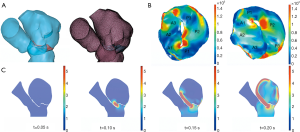

Comsol Multiphysics 5.5 (COMSOL Inc., Stockholm, Sweden) was used to reconstruct the mesh of the left heart system (Figure 4). Before being imported into Comsol Multiphysics, the mesh quality of the left heart model was simply refined using the remesh function in 3-matic. “Boundary partitioning” and “Repair tolerance” were also adjusted appropriately after the mesh was imported into COMSOL, to further refine its quality. In material science, it is assumed that the blood is an incompressible Newtonian fluid: blood viscosity μ =0.0035 kg/ms; density ρ =1,050 kg/m3. A fluid-solid interaction (FSI) multiphysics interface was used to model the physics which are involved when blood and heart tissue affect each other. It was assumed that heart tissue is rigid, impermeable, and wall sliding. Heart rate was assumed to be 75 beats/min and the cardiac cycle was t =0.8 s. Blood flow in the left heart conforms to the following continuity equation of mass conservation and 3D unsteady Navier-Stokes equation of momentum conservation: